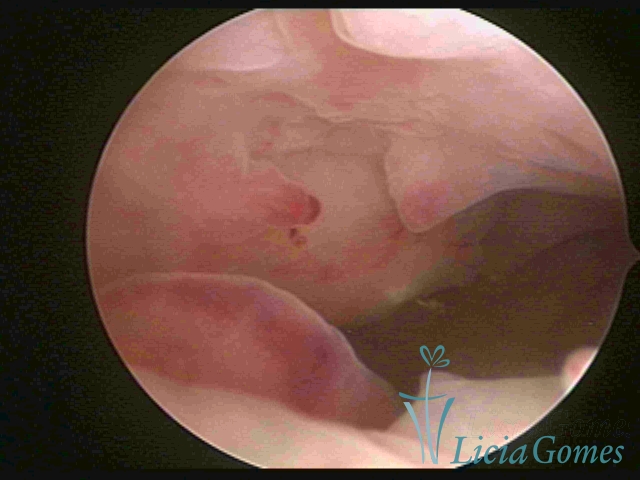

Polypoid hypertrophy is viewed when the endometrial growth is more pronounced and, since the space of the uterine cavity is limited, it presents the formation of folds or grooves, simulating pseudopolypoid or polypoid lesions.

In simple hypertrophy, there is an increase in the endometrial thickness with a protuberance of the glandular punctuate, differing from the proliferative endometrial pattern by the loss of superficial reticular vascularization. Another form of simple hyperplasia is the cystic glandular hyperplasia, which also presents cystic lesions intercalated to the hypertrophic endometrium.

Complex Hyperplasia has a pseudopolypoid aspect which resembles cerebroid tissue or with decidual reaction. The superficial vascularization is more evident, presenting vessels in the shape of corkscrew or spiral.